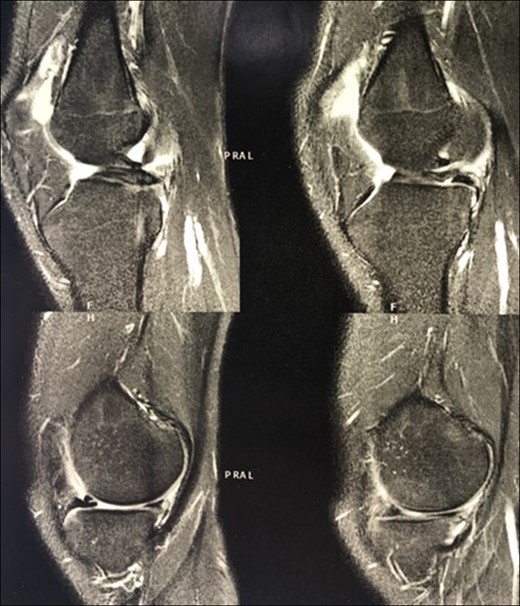

The patient underwent arthroscopic ACL reconstruction using ipsilateral flexor tendons as graft, PCL reconstruction using contralateral flexor tendons as graft and partial meniscectomy (Figs 3–5).

Arthroscopy surgery view during cruciate ligaments reconstruction. Note in (A) and (B) the ligaments absence. The lateral meniscus has not its bone tibial insertion of the posterior horn (*), which continued with the anterior meniscus femoral ligament (Humphry), which was hypertrophied (**). LFC, lateral femoral condyle.

Another interesting detail noted in this case was the absence of the tibial bone insertion of the posterior horn of the lateral meniscus, which in this case was continued with a hypertrophied meniscal femoral ligament (Fig. 3). Perhaps an anatomical attempt to stabilize the knee, but without success.